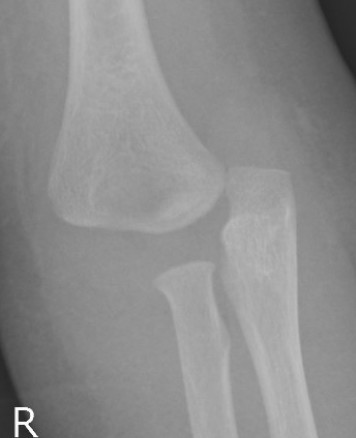

Xray

Distal physis not ossified < 1 year

- radius and ulna lose normal association with distal humerus

- posteromedial displacement of the ulnohumeral joint

- appears like an elbow dislocation

- disruption of radio-capitellar line